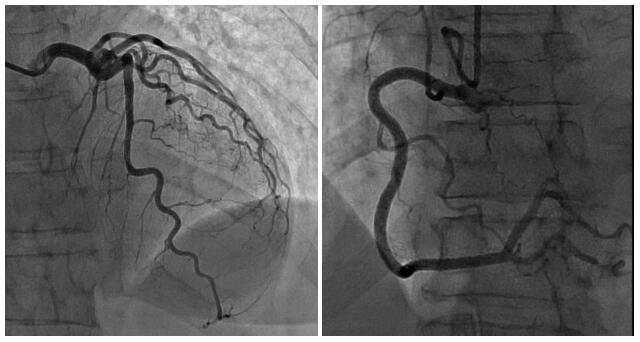

An electrocardiogram (EKG) showed sinus rhythm with normal axis, normal R wave progression and no significant ST-T wave changes. The patient was started on aspirin, high intensity statin, ticagrelor and heparin drip in the setting of elevated troponin. A transthoracic echocardiogram (TTE) showed left ventricular ejection fraction of 30–35% with severe hypokinesis of the entire mid- and apical walls (Fig. 1). Considering the echocardiogram findings and the patient’s persistent chest pain, left heart catheterization was performed. This showed nonobstructive coronary arteries with no coronary vasospasm (Fig. 2). With the absence of any obstructive coronary artery disease on cardiac catheterization, the TTE findings were consistent with Takotsubo/stress cardiomyopathy. Over the course of her hospital stay, the patient’s chest pain improved, and her condition stabilized. She was discharged on lisinopril, carvedilol, atorvastatin and aspirin. She was counseled to cease cocaine use. She was instructed to follow up with cardiology as out-patient. Cardiology follow-up at 60 days showed improvement in her clinical state and also echocardiogram findings.

Figure 2.

Normal coronary angiogram

Cocaine is a highly addictive crystalline alkaloid that is the most frequent cause of drug-related deaths in the United States [7]. Cocaine mediates its effect by inhibition of norepinephrine, epinephrine, dopamine, and serotonin reuptake in the presynaptic neurons [7]. This causes overstimulation of alpha- and beta-adrenergic receptors. The resulting catecholamine surge is associated with a variety of cardiovascular abnormalities including myocardial infarction (MI), arrhythmia, cardiomyopathy and congestive heart failure [8]. Long-term cocaine use is associated with left ventricular hypertrophy and prolonged deceleration time [9]. The correlation between cocaine use and TCM can depend on factors such as the time of presentation in the hospital, illegal use and short half-life of cocaine, disparity in health care and other cardiac comorbidities pointing towards diagnoses with similar presentation. In our case the patient presented with chest pain a few days after consuming cocaine. Although a definite causal relationship cannot be ascertained, the close temporal association between the use of cocaine and the rapid onset of symptoms suggests that cocaine might be the trigger for the development of TCM. The echocardiogram having showed severe hypokinesis of the mid- and apical wall, and the left heart catheterization having showed no evidence of coronary artery disease, a diagnosis of TCM was made.